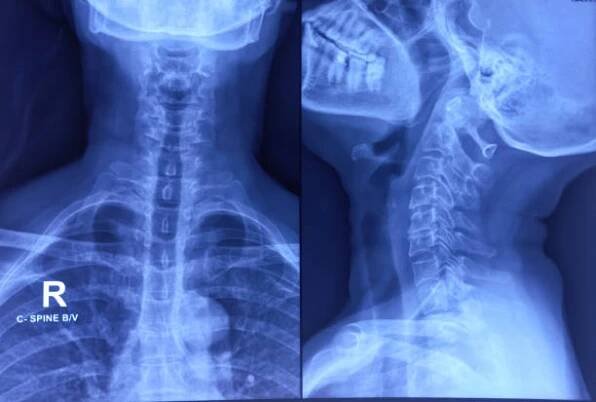

rentgen krční páteře se spondylózou krční páteře. okrajové osteofyty. cervikální spondylóza. - skřípnutý nerv - stock snímky, obrázky a fotky

Jaké jsou příznaky dorzálních osteofytů?Dorzální osteofyty jsou osteofyty, které se tvoří na zadní straně páteře. Tyto osteofyty mohou způsobovat bolest v dolní části zad, která může vyzařovat do nohou. Tyto osteofyty mohou být vidět na rentgenových snímcích.

Jaké jsou rizika osteofytů na bederní a krční páteři?Osteofyty na bederní a krční páteři mohou způsobovat bolest a omezení pohybu. Tyto osteofyty mohou být vidět na rentgenových snímcích. Rizika zahrnují zhoršení stavu a možnost komplikací, jako je například stlačení nervů.